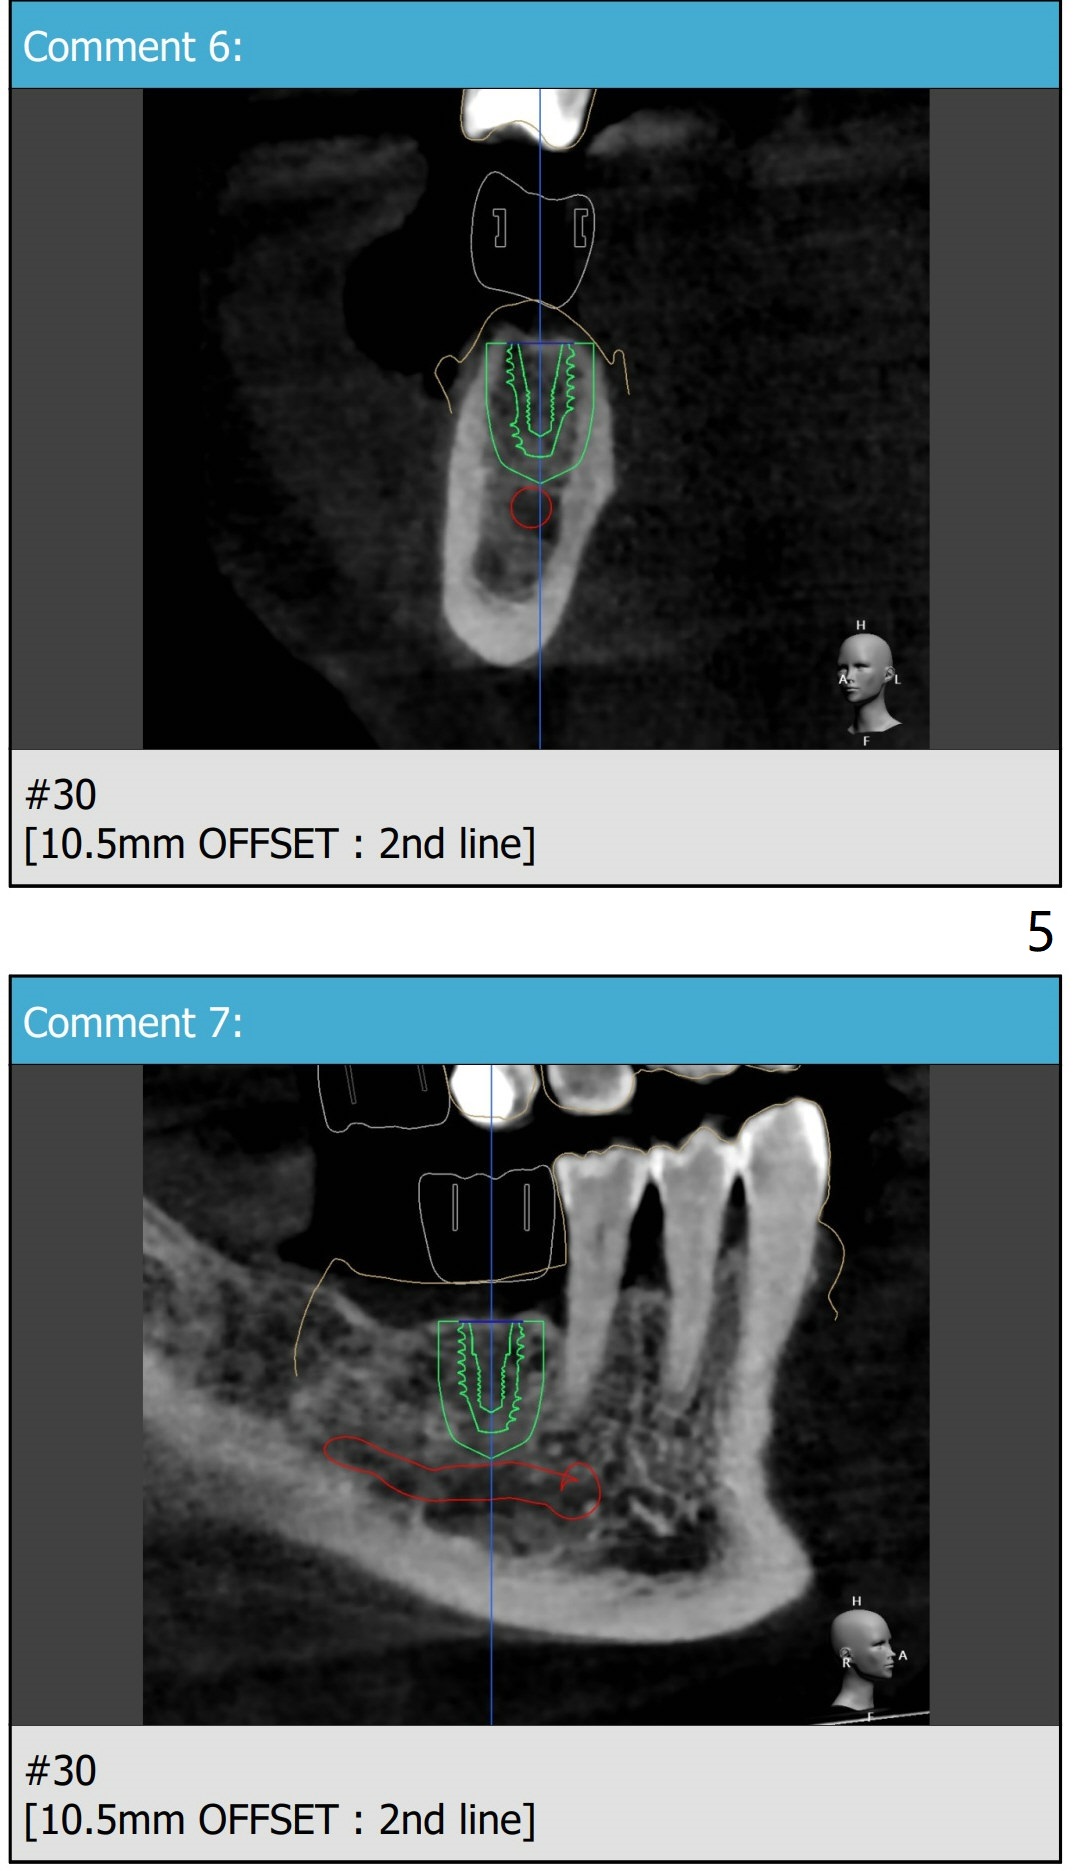

66岁男缺失右上,右下第一磨牙许久,需要上颌窦提升。Because of sinus lift, make a little sticky bone, considering autogenous bone from #30 and 3 osteotomy sites. Tube x1.